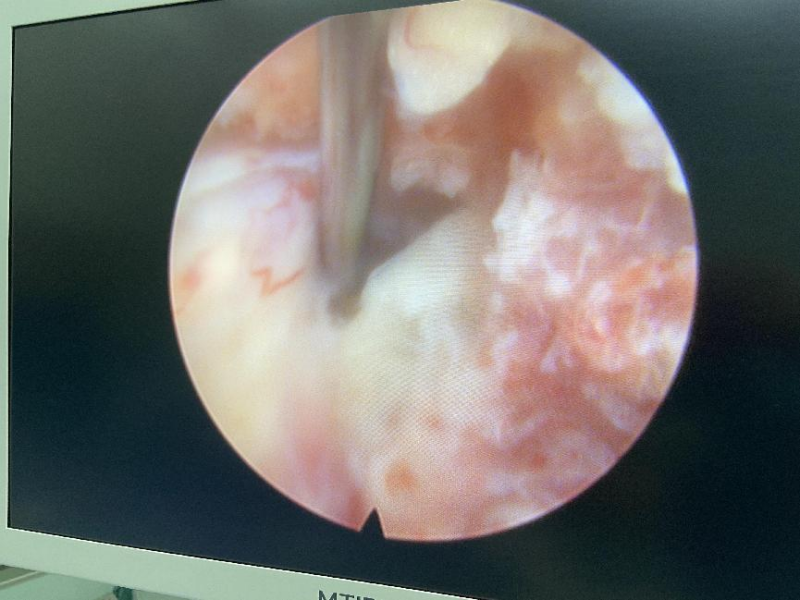

1.手术现场

2.镜下显露卡压神经的椎间盘

颈椎后路“钥匙孔手术”属于微创手术,可采用全麻及局麻方式,通过术前精准定位,术中靶向穿刺,借助工作通道可直达突出的椎间盘位置,在脊柱内镜辅助下利用动力系统在颈椎椎板和关节突之间磨除少许骨质,形成一个直径6-8毫米左右“钥匙孔”大小的减压窗,在这个“钥匙孔”内完成突出髓核的摘除,手术切口不到1厘米。手术创伤小,时间短,出血少,恢复快。